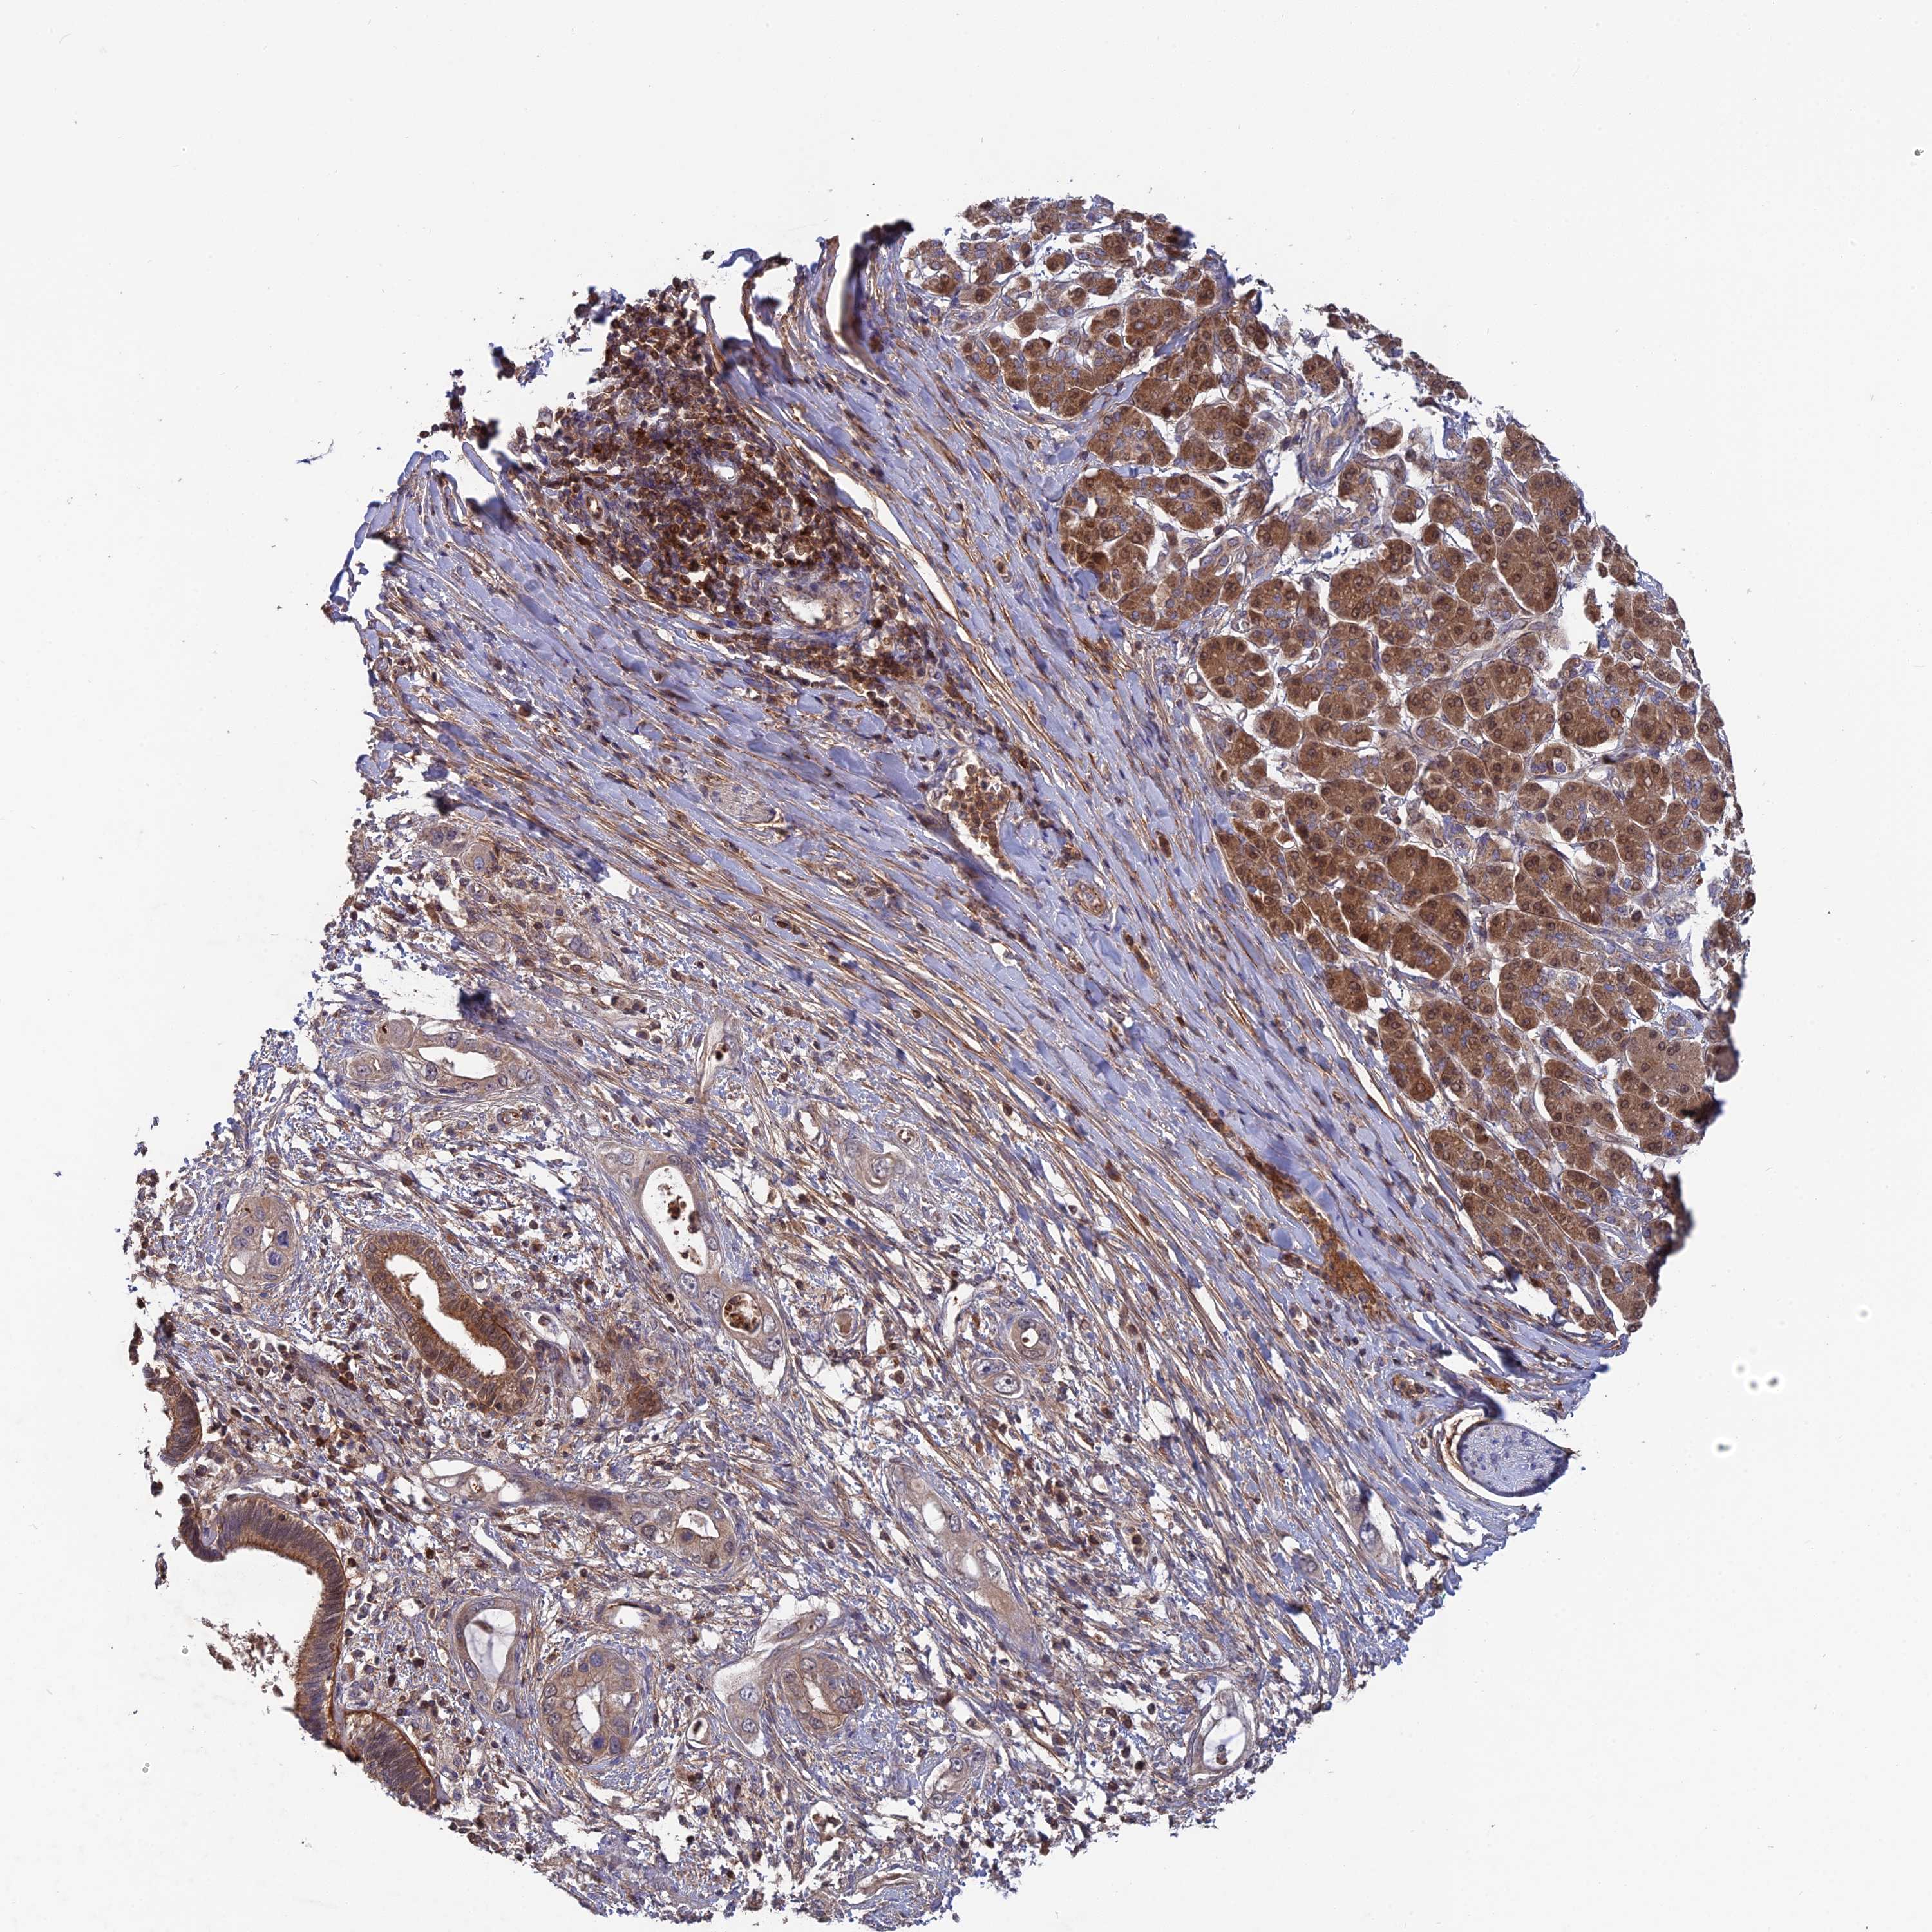

PANCREATIC CANCER - Protein expressioni

A mouse-over function shows sample information and annotation data. Click on an image to view it in a full screen mode. Samples can be filtered based on level of antibody staining by selecting one or several of the following categories: high, medium, low and not detected. The assay and annotation is described here.

Note that samples used for immunohistochemistry by the Human Protein Atlas do not correspond to samples in the TCGA dataset.

Antibody stainingi

Antibody staining in the annotated cell types in the current human tissue is reported as not detected, low, medium, or high, based on conventional immunohistochemistry profiling in selected tissues. This score is based on the combination of the staining intensity and fraction of stained cells.

Each image is clickable and will lead to virtual microscopy that enables deeper exploration of all samples and also displays staining intensity scores, fraction scores and subcellular localization as well as patient and tissue information for each sample.

Antibody HPA042620

Staining

High

Medium

Low

Not detected

Intensity

Strong

Moderate

Weak

Negative

Quantity

>75%

75%-25%

<25%

None

Location

Nuclear

Cytoplasmic/membranous

Cytoplasmic/membranous,nuclear

Adenocarcinoma, NOS